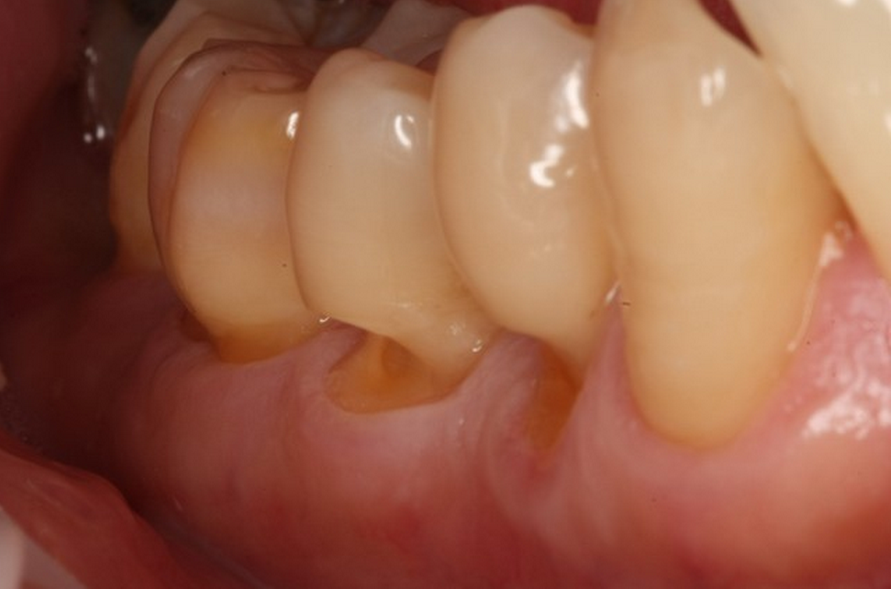

Case Study 2: Severe Abrasion with Secondary Abfraction

Patient Profile: 62-year-old female presenting with cervical sensitivity and noticeable gingival recession.

Clinical Findings:

- Pronounced V-shaped notches at the cervical third of multiple teeth

- History of aggressive brushing with medium-bristled brush

- Visible evidence of occlusal wear facets suggesting parafunctional activity

- Radiographic evaluation showing no periapical pathology

Diagnostic Assessment: Primary abrasion from improper brushing technique compounded by abfraction lesions from occlusal stress.